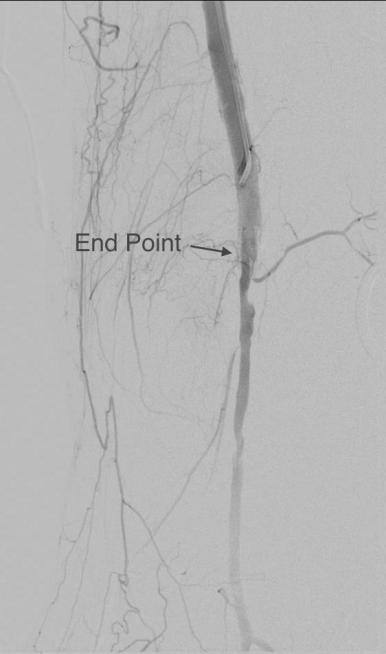

The patient’s right common femoral artery was exposed in the usual manner. Wire access across the occluded external iliac artery was achieved from a puncture of the common femoral artery. Remote endarterectomy (EndoRE) was performed over a wire from the common femoral artery to the external iliac artery origin (pictures below).

The patient was operated on in a hybrid endovascular OR suite. A right groin incision was made to expose the common femoral artery for endarterectomy and left common femoral access was achieved for angiographic access, but also to place a wire across the occlusion into the common femoral artery.

All actions on the external iliac artery plaque are done with an up-and-over wire, allowing for swift action in the instance that arterial perforation or rupture occur. This event is exceedingly rare when the operation is well planned. With this kind of access, an occlusive balloon or repairing stent graft can be rapidly delivered.

The common femoral endarterectomy is done from its distal most point and the Vollmer ring is used to mobilize the plaque. A Moll Ring Cutter (LeMaitre Vascular) is then used to cut the plaque.

The plaque is extracted and re-establishes patency of the EIA.

The plaque end point is typically treated with a stent -in this case, the common iliac plaque was also treated.